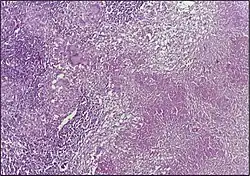

![]() |

Dysgerminoma | Dysgerminoma characterized by uniform cells resembling primordial germ cells separated by fibrous septa with lymphocytes. | Category: Histopathology of ovarian dysgerminoma | Ovarian dysgerminoma |